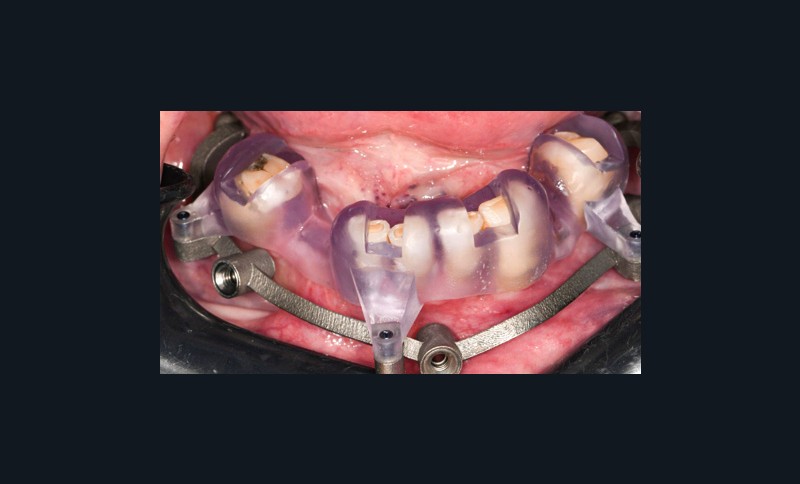

Un premier étage, appelé guide base, est fixé sur le maxillaire à implanter et servira de socle pour les étages supérieurs à empiler (fig. 2). Il doit être aussi rigide que stable pour supporter les contraintes pendant toute la durée de l’intervention : celles du forage implantaire comme celles des poses et déposes des étages supérieurs. Son bon positionnement est donc crucial car il déterminera celui des autres étages. Il peut également servir de repère en fin de procédure, tel un guide de scannage, pour réaliser une empreinte optique (fig. 3). Les appuis sont aussi divers qu’avec un guide statique conventionnel :

- appui dentaire : il est le plus fiable car son positionnement est permis grâce à des points fixes (fig. 4). Il reste bien sûr dépendant de la précision de l’alignement entre le STL de l’empreinte optique et le DICOM de l’examen CBCT ;